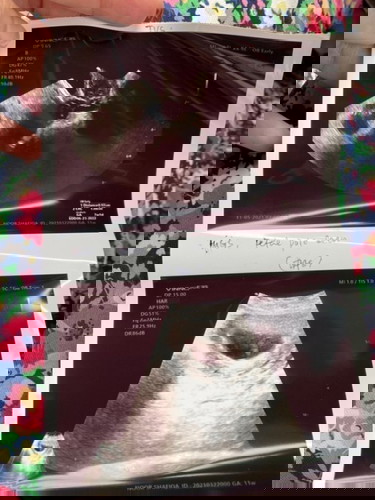

Scan baby tenggelam timbul

Salam, ada tak siapa yang ada pengalaman scan baby awal2 1st trimester tenggelam timbul2 bila scan? Saya risau, haritu scan 6 week dah nampak jantung dengan janin, lepas 3 weeks tu last week saya scan semula, waktu scan tak nampak baby.. baby macam tenggelam timbul macam tu.. Bila scan ada nampak jantung, cuma doc tak dengar je sebab kecik lagi.. Gambar bawah ialah last week scan.. Dan harini pulak saya scan lagi lepas seminggu, sama saja tenggelam timbul baby.. doc takut janin tak membesar ikut weeks, dr suruh saya tunggu 2 minggu utk scan semula.. tadi pulak scan macam lagi teruk lak nampaknya berbanding lepas, tak dapat nak ukur baby berapa weeks.. Yang ni second pregnancy saya, first saya miscarriage awal bulan 4/21. Saya sangat risau, doakan saya ada rezeki baby kali ini 😭 #advicepls #1stimemom #pleasehelp #firstbaby